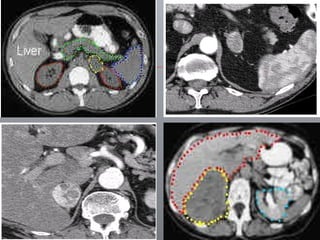

Diagnóstico  Clínico  / laboratorial: variável USG Imagens: TC RNM